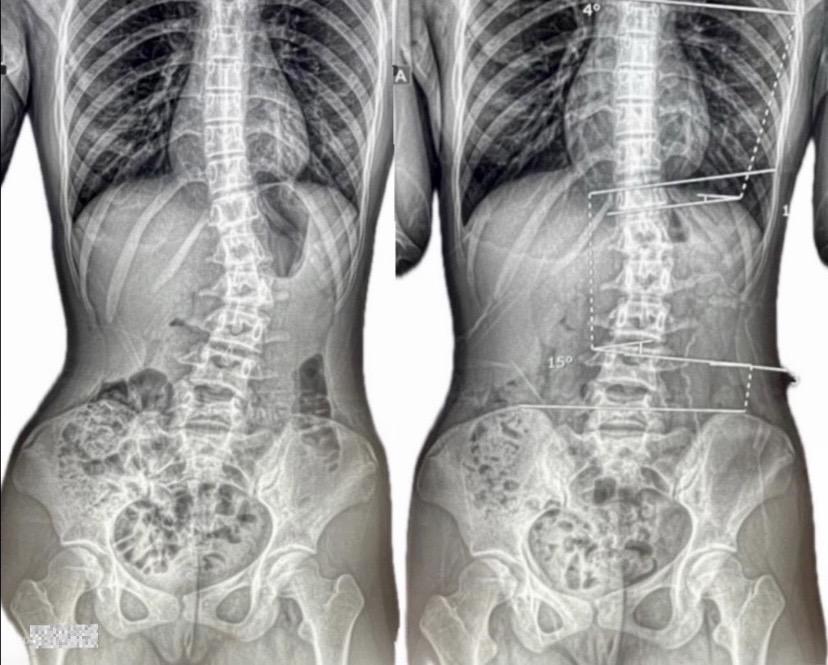

中〜高校生の改善例(女の子)

病院では「定期的な経過観察が必要」と言われ、ただただ経過観察をしていく中で、「他に何かできることはないのか…」「進行度合いの確認だけでなく根本的に改善させるような方法はないのか…」との親御様の切なる思いからインターネットで検索され当院に来院されました。現在も尚、病院でのリハビリ指導と当院でのカイロプラクティックケアに運動指導などを行いながら、さらなる改善へ向けて取り組まれています。

※これは個人の感想と画像の結果であり施術の効果を保障するものではありません。また効果には個人差があります。